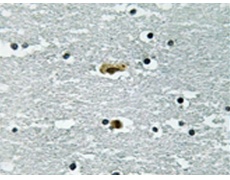

IHC positive control: |

Human brain tissue |